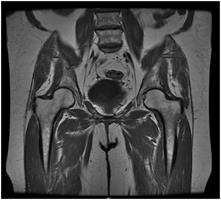

Your doctor has ordered a MRI (Magnetic Resonance Imaging) of your pelvis. MRI uses a magnetic field, radio waves and a computer to create images soft tissues, bones, and internal body structures. MRI of the pelvis allows physicians to examine the pelvic anatomy to rule out any structural abnormalities.

MRI of the pelvisPelvis MRI